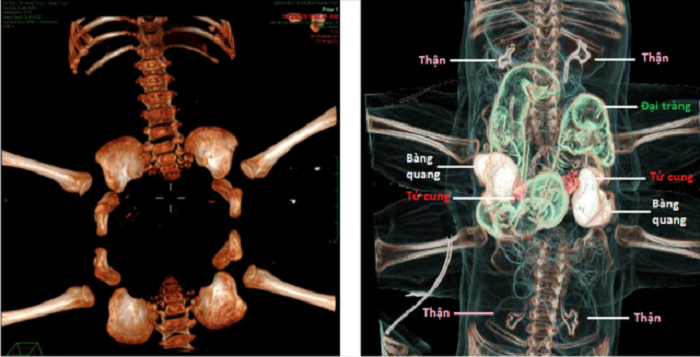

Các bác sĩ khoa chẩn đoán hình ảnh xác định hai bé gặp nhiều bất thường tại vùng bụng chung. Về tiêu hóa, hai bé có chung một phần hồi tràng, một khung đại tràng và chỉ một lỗ hậu môn.

Về hệ thận niệu, các bé có hai bàng quang nằm hai bên ổ bụng chung, mỗi bàng quang được hai niệu quản xuất phát từ hai bé đổ vào thay vì của cùng một bé. Về cơ quan sinh dục, hai bé có tử cung âm đạo đôi. Ngoài ra hai bé còn bị hở khớp mu, khung chậu xếp thành một vòng tròn.